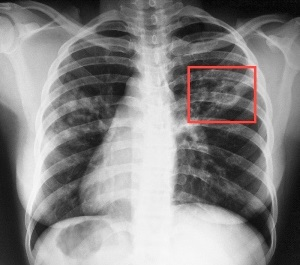

Единственным способом выявить болезнь на ранних этапах развития является флюорографическое обследование.